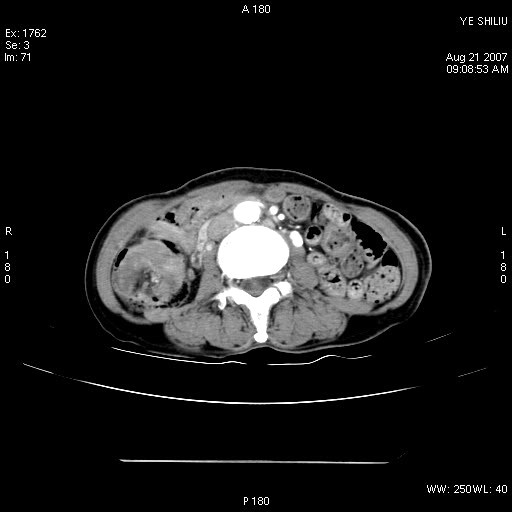

回盲部腺癌

患者,女,74岁,腹痛一周。开始为脐周疼痛,后转移至右下腹。治疗经过:门诊拟急性阑尾炎收内科治疗,b超示胆囊结石、胆囊炎转外科。拟行胆囊切除术前检查ct。